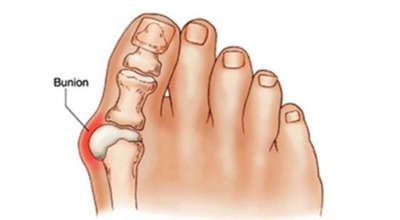

엄지발가락이 두 번째 발가락 쪽으로 과도하게 휘고, 엄지발가락과 연결되는 중족골이 반대로 안쪽으로 기울어지며 발가락이 발등 쪽으로 휘거나 회전(엄지발가락 축을 중심으로 내측으로 회전; 회내)하는 삼차원적인 변형을 말합니다.

육안으로 확연히 엄지발가락의 변형이 보이며, 초기에는 굳은살이 생기고 약간의 통증도 동반됩니다. 엄지발가락의 돌출 부위에 통증이 발생하는데, 이 부위가 신발에 자극을 받아 두꺼워지고 염증이 생겨 통증이 유발됩니다. 발바닥에 굳은살이 생기면 정상적인 보행이 어려워지고, 심한 경우에는 통증 때문에 신발 착용이나 정상적인 보행도 힘들어질 수 있습니다. 증상이 지속적으로 악화되면 엄지발가락이 겹치거나 탈구될 수도 있습니다.

초기 단계에서는 건막류(두꺼운 혹)를 절제하는 건막류절제술을 시행합니다. 돌출된 건막류를 절제하여 각도를 교정하고, 짧아진 근육이나 연부조직을 늘려주는 비교적 간단한 수술입니다. 다른 발가락의 변형이 동반되거나 뼈의 과잉 성장이 심한 경우에는 뼈를 깎고 방향을 돌린 뒤 발가락이 똑바로 펴지도록 철사로 고정하는 교정절골술을 시행합니다. 양쪽 발이 모두 변형된 경우, 대개 한 번에 한쪽만 수술합니다.